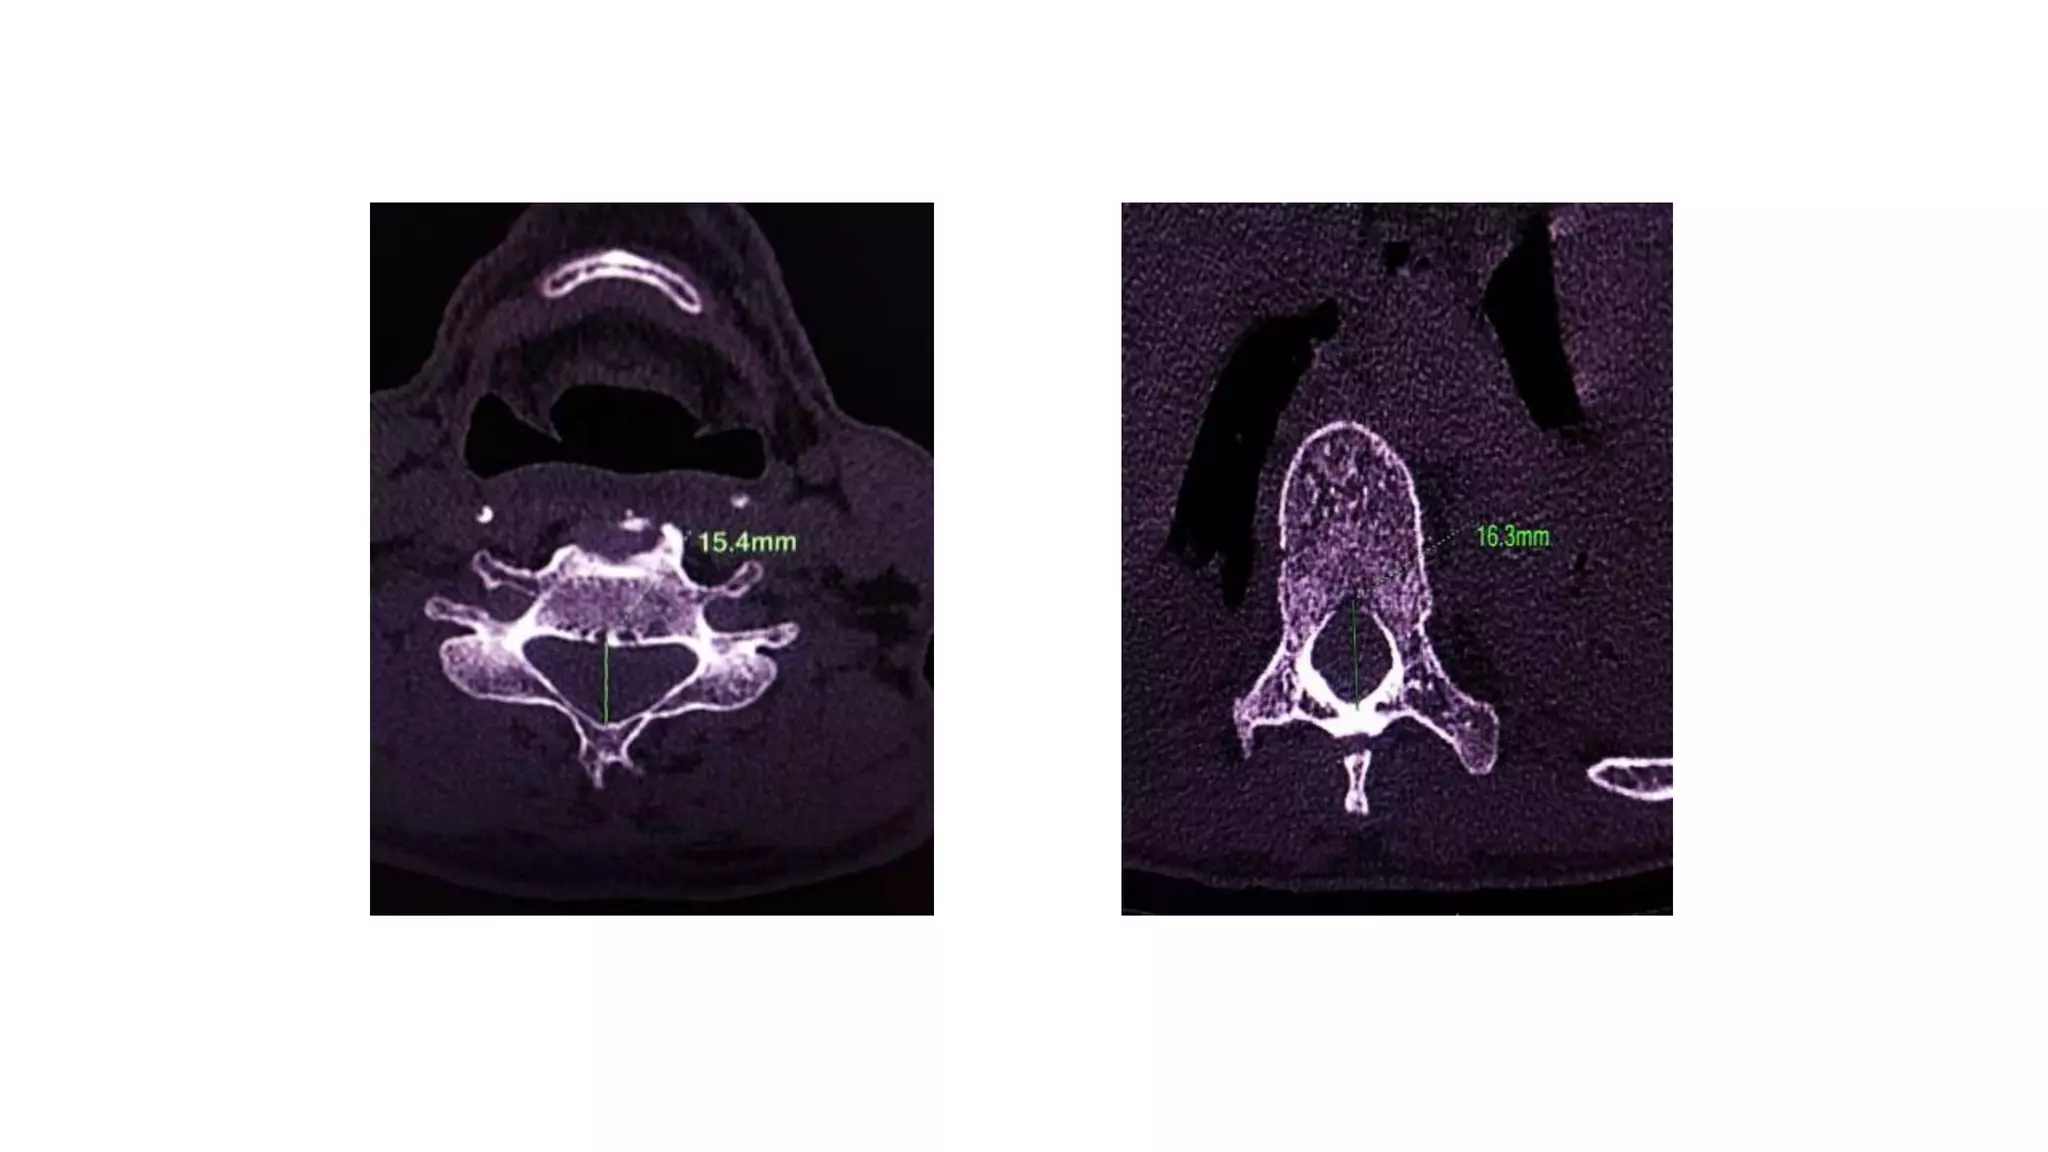

Normal Spinal canal diameters

CERVICAL SPINE

At the cervical levels C4–C7 the average antero-

posterior diameter is 17 mm and values below 14 mm

are considered critical.

At the lumbar level a classification of spinal stenosis was

suggested by Benoist:

• Severe stenosis (< 10 mm)

• Moderate stenosis (10–12 mm)

• Mild stenosis (12–14 mm)

Normal Spinal canaldiameters THORACIC SPINE CERVICAL SPINE

At the cervicallevels C4–C7 the average antero- posterior diameter is 17 mm and values below 14 mm are considered critical. At the lumbar level a classification of spinal stenosis was suggested by Benoist: • Severe stenosis (< 10 mm) • Moderate stenosis (10–12 mm) • Mild stenosis (12–14 mm)